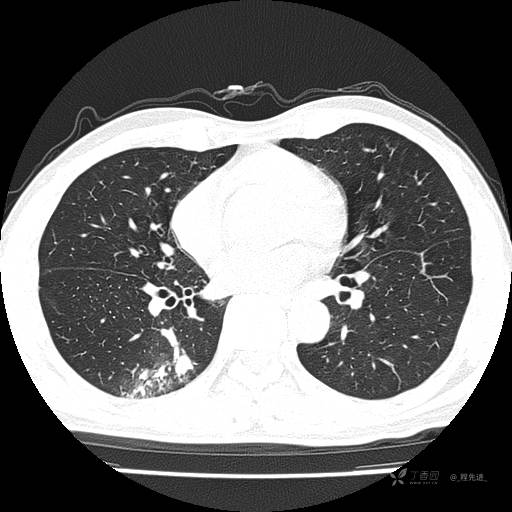

2月特别精彩病例|咳嗽、咳痰20余天,典型病例分享【结果已公布】

呱呱叫了 等 2 位达人已点赞患者性别:男

患者年龄:51岁

主诉:咳嗽、咳痰20余天

简要病史:20余天前开始出现咳嗽、咳痰症状,阵发性刺激性咳,白色粘痰,不易咳出,无发热,无咯血,无恶心、呕吐等不适,未诊治,咳嗽、咳痰症状持续存在。

体格检查:T:36.3 ℃ P:79 次/分 R:20 次/分 BP:128/64 mmHg,神志清楚,呼吸平稳,双肺呼吸音粗,右下肺闻及细湿性啰音。心率79次/分,节律整齐,各瓣膜听诊区未闻及病理性杂音。腹部未见异常,双下肢无水肿。

辅助检查:我院门诊胸部CT示:如下。心电图:窦性心律;正常心电图。